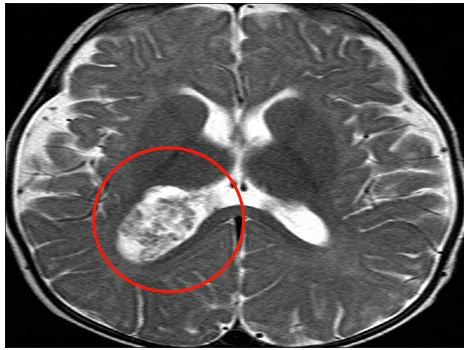

65歲的湯姆是一名與腎癌抗?fàn)幍膽?zhàn)士,即便身患重病,他也從未放棄對生命的熱忱與追求。然而,命運再次向他發(fā)起挑戰(zhàn)——出現(xiàn)認(rèn)知障礙后,醫(yī)生在他的腦室中發(fā)現(xiàn)了一處腫瘤。鑒于他以往的癌癥病史,臨床首先推測這很可能是一處腎癌腦轉(zhuǎn)移瘤。

A與B:術(shù)前軸位增強T1加權(quán)MRI

這臺手術(shù)由巴特朗菲教授主刀,成功地將腫瘤完整切除。而最令人意外的是,最終的術(shù)后病理結(jié)果逆轉(zhuǎn)了所有人的預(yù)判:那并非惡性的轉(zhuǎn)移瘤,而是良性脈絡(luò)叢乳頭狀瘤。這個結(jié)果證明湯姆的選擇是對的。(該案例來自于INC巴特朗菲教授的《Ventricular Tumors》)

術(shù)后CT證實無殘留(D)